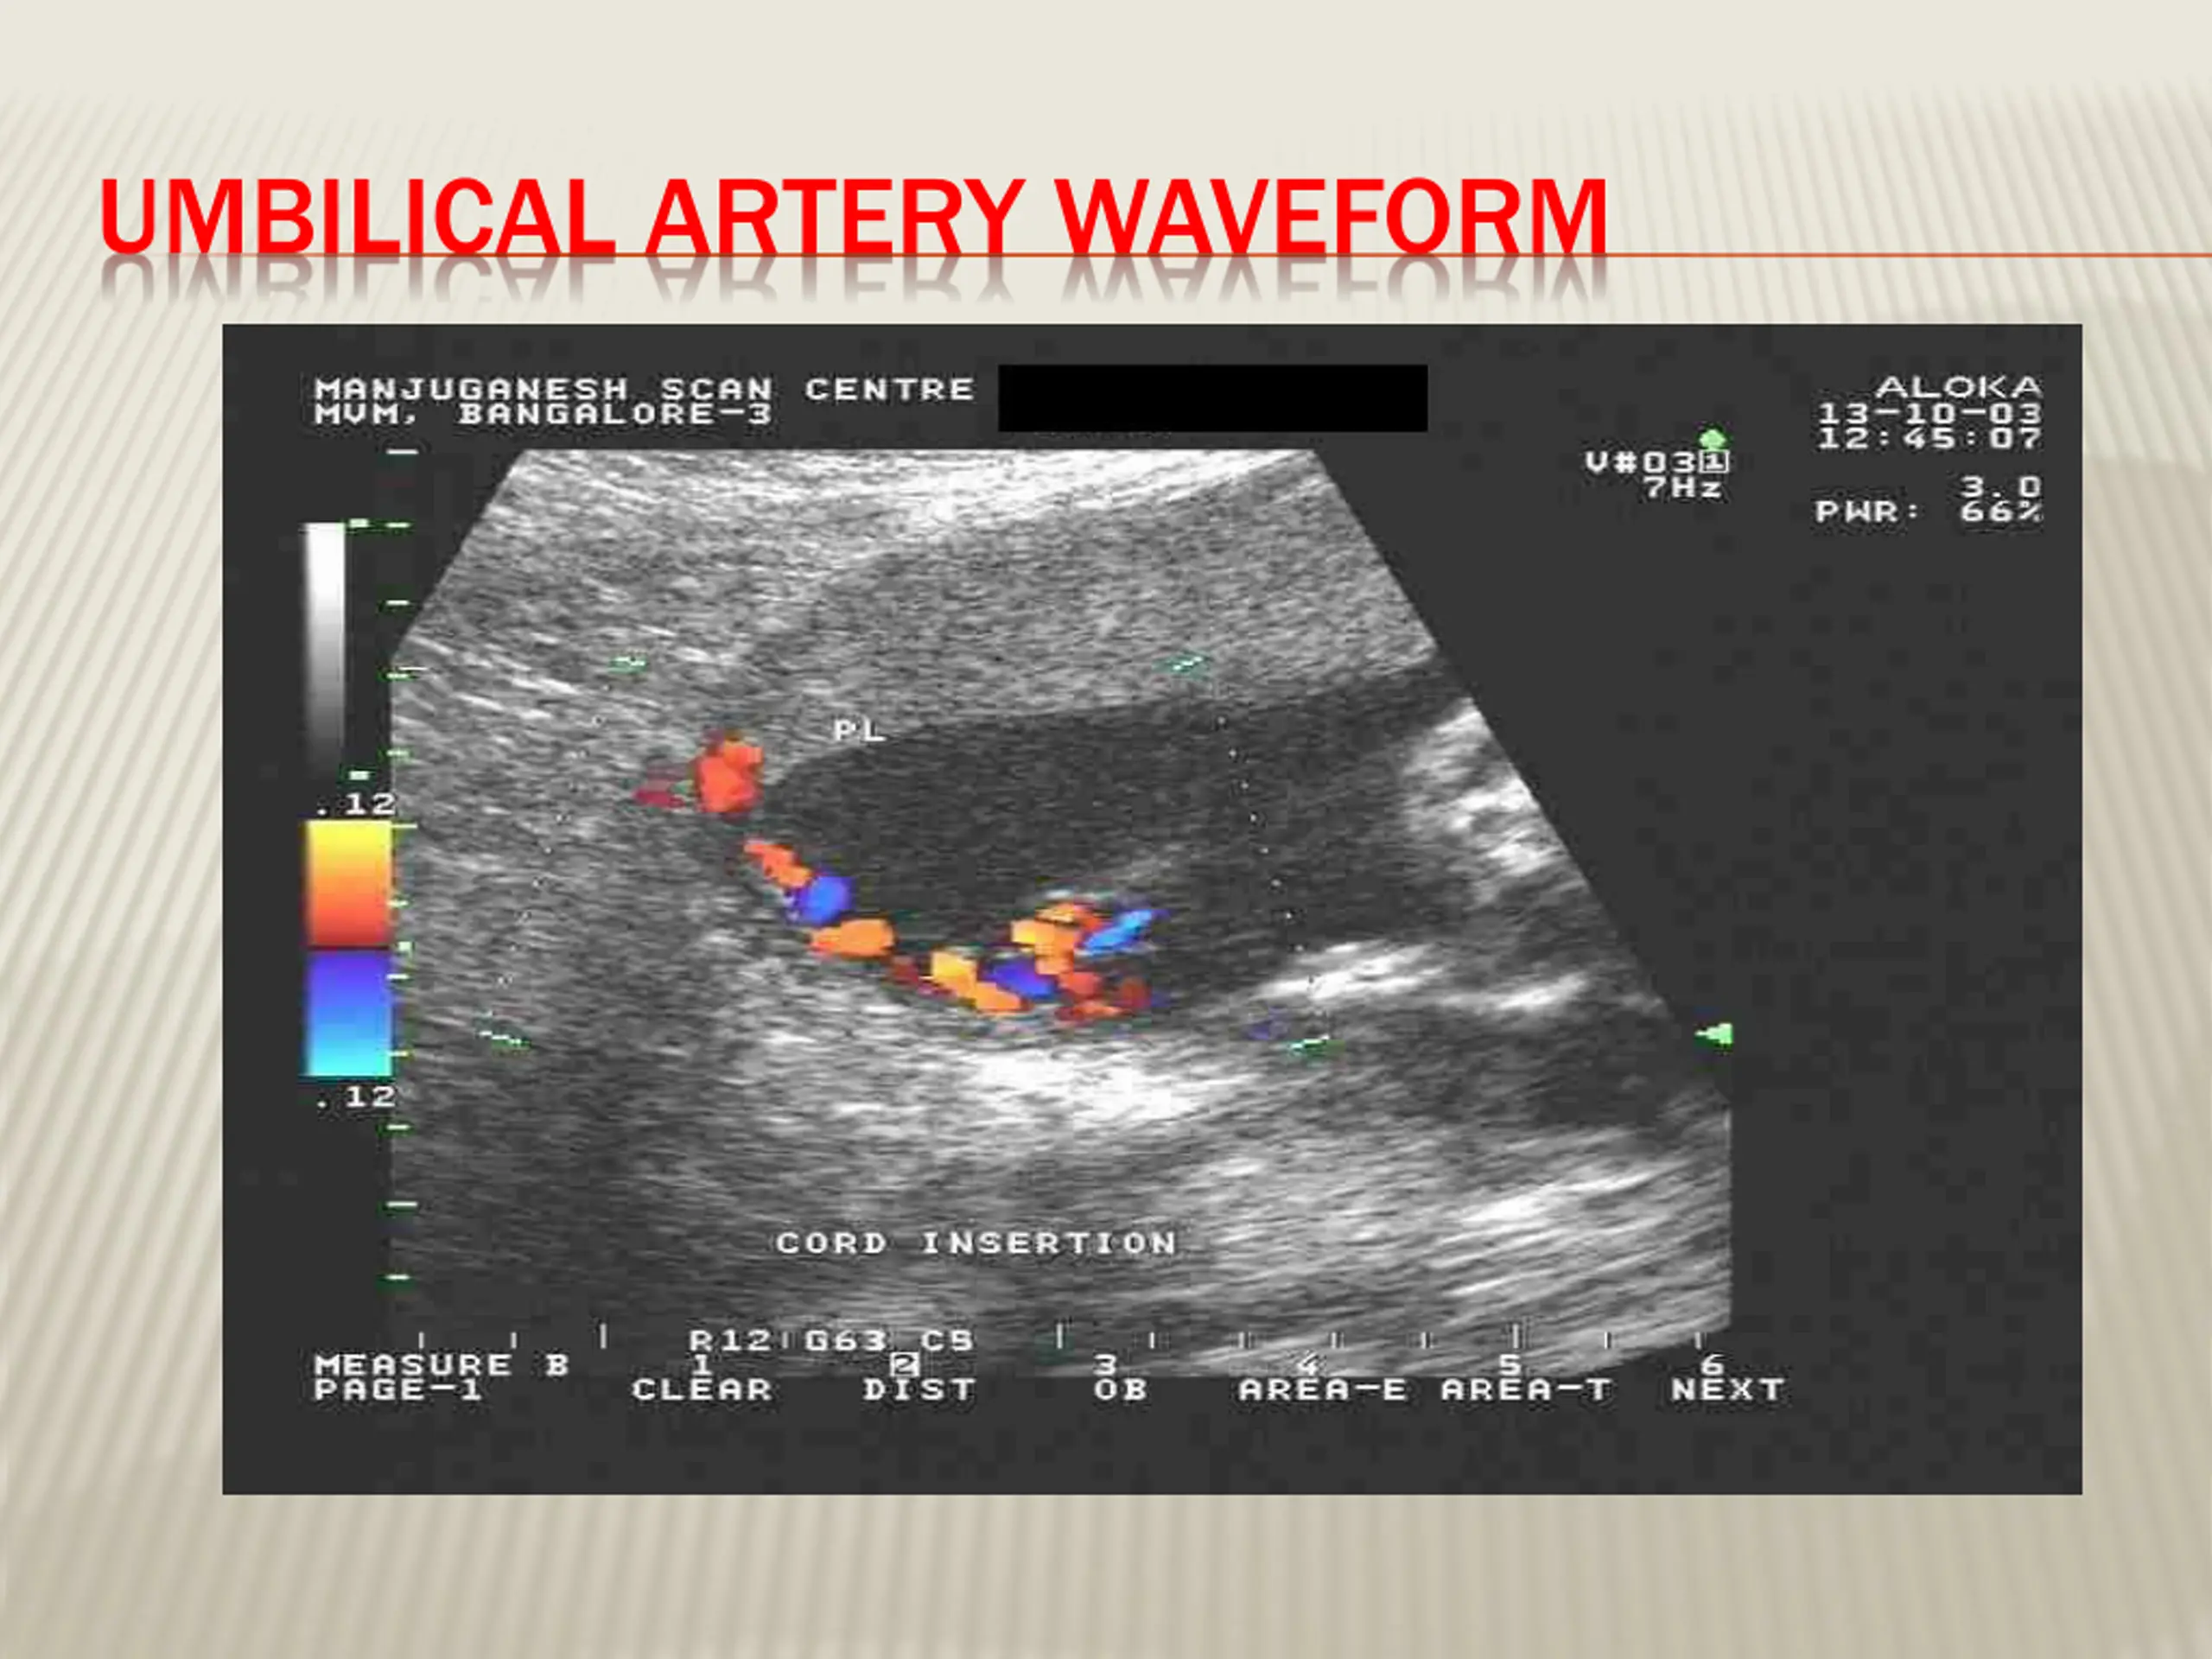

19. UMBILICAL ARTERY WAVEFORM

18. DOPPLER VELOCIMETRY Measurement of blood flow velocities in maternal & fetal vessels Reflects feto-placental circulation Doppler indices from Uterine Artery cerebral artery cerebral artery (MCA) In IUGR : absent or reversed EDF (end diastolic flow) : associated with fetal hypoxia Uterine Artery & Middle Middle